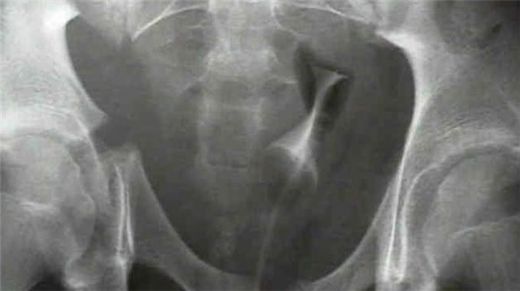

Tanı Yöntemleri Leğen kemiği kırığının tanısı, genellikle aşağıdaki yöntemlerle konur:

Leğen kemiği, pelvis bölgesinde yer alan ve vücut ağırlığını taşıyan önemli bir yapıdır. Leğen kemiği kırığı, genellikle travmatik olaylar sonucunda meydana gelir ve ciddi sağlık sorunlarına yol açabilir. Bu makalede, leğen kemiği kırığının belirtileri, tanısı ve tedavi yöntemleri üzerinde durulacaktır. Leğen Kemiği Kırığı Nedir?Leğen kemiği kırığı, pelvisin yapısında meydana gelen bir yaralanmadır. Bu kırıklar, genellikle yüksek enerjili travmalar (örneğin, trafik kazaları, düşmeler veya sportif yaralanmalar) sonucunda ortaya çıkar. Leğen kemiği, birçok önemli organı korumasının yanı sıra, vücudun dengesini sağlamada da kritik bir rol oynar. Belirtiler Leğen kemiği kırığının belirtileri şunları içerebilir: